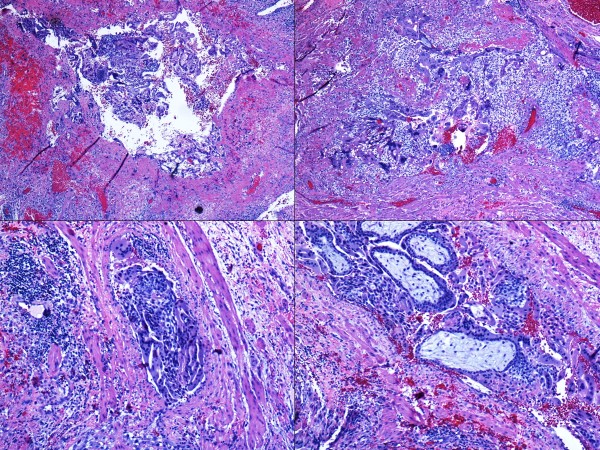

COMPLETE HYDATIDIFORM MOLES:

- Grossly large amount of tissue (5 cm and more) with sometimes large ballooned villi (>1 cm).

- Presence of cisterns, circumferential or almost circumferential trophoblastic proliferation and trophoblastic inclusions (figure 3-4).

- Blue myxoid stroma with karyorrhexis (figure 5).

- Atypical and exaggerated implantation site with large trophoblasts, at least three times larger than decidual cells (figure 6).